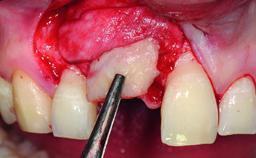

Replacement of an Upper Right Central Incisor with a Root Fracture, Early Placement of an RC Bone Level Implant, Variobase Abutment

A healthy 28-year-old female patient presented for a consultation on treatment options to restore her upper right central incisor. At the clinical examination, the tooth responded to percussion and palpation. The gingiva was red and slightly swollen, with a mid-facial probing depth of 10 mm. The upper right lateral incisor showed no signs or symptoms, did not respond to exploration and percussion, and the vitality test was positive. The periapical radiograph revealed that tooth 11 had been endodontically treated, with no lesion evident at the apex. A small radiopaque calcified structure surrounded by a narrow radiolucent zone (3 × 3 mm) was present at the apex of tooth 12.